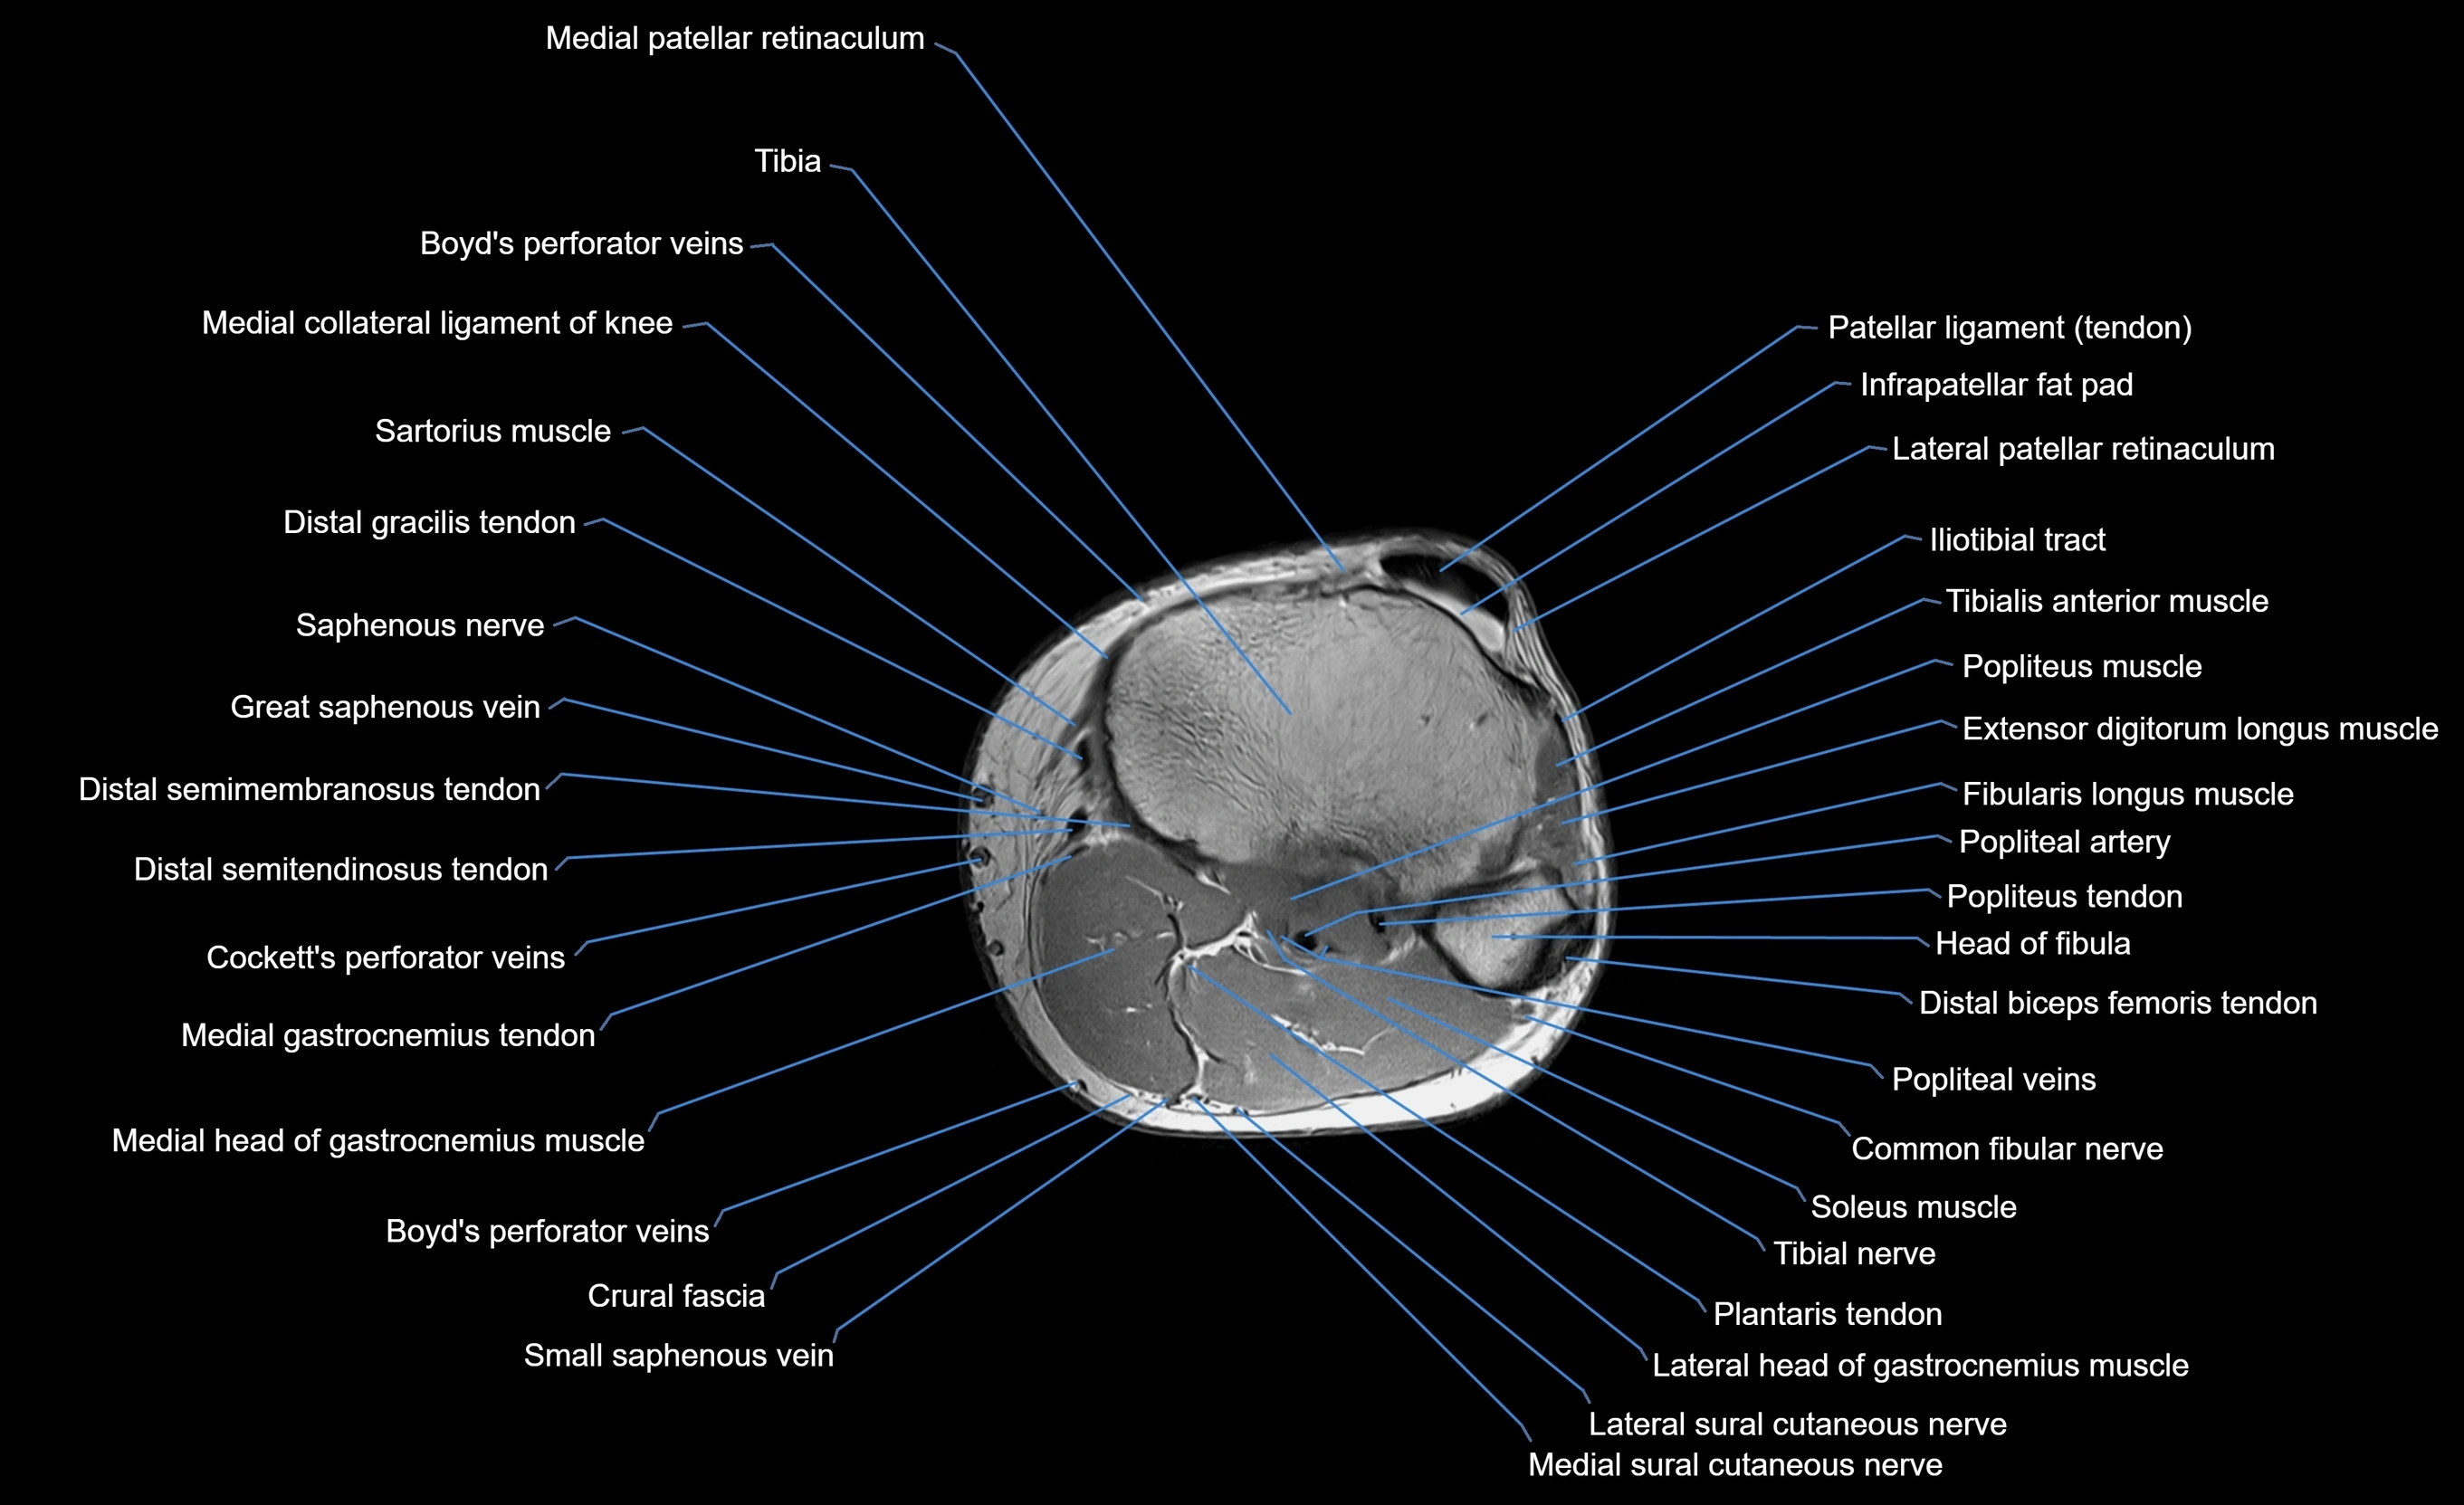

MRI image